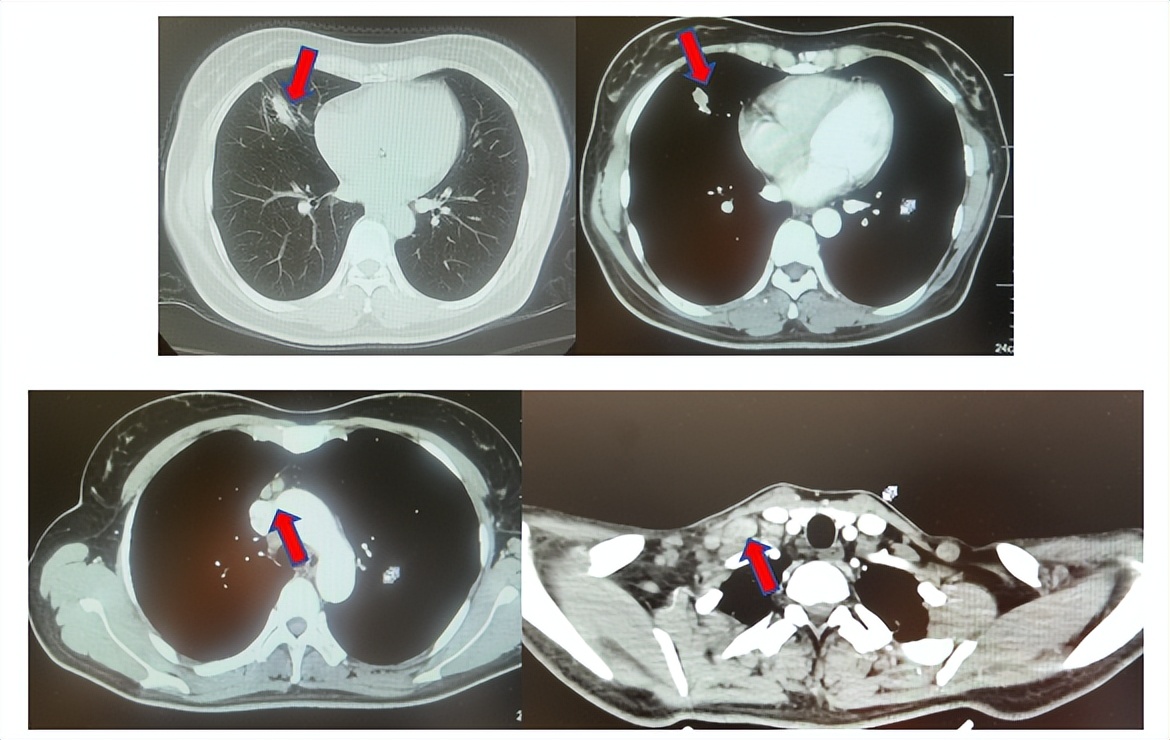

图2:上两图分别展示2021年5月患者达到最佳疗效时肺CT肺窗及纵隔窗肺内病灶及肺门淋巴结影像,下三图表示最佳疗效时脑MRI影像

患者进入到二线治疗,该患者再次符合我科“优替德隆对照多西他赛治疗含铂化疗失败的局部晚期或转移性非小细胞肺癌的III期、开放、随机对照临床试验”经随机进入多西他赛组,截止至目前患者已行多西他赛治疗19周期,期间评效为SD(图3),二线无进展生存至今为14个月,患者总生存期截止目前超过92个月(整体治疗过程如图4所示)。

图3:上两图分别展示2024年1月患者一线进展时肺CT肺窗及纵隔窗肺内病灶影像,下两图表示2024年12月患者二线治疗间期评效时肺CT肺窗及纵隔窗肺内病灶影像